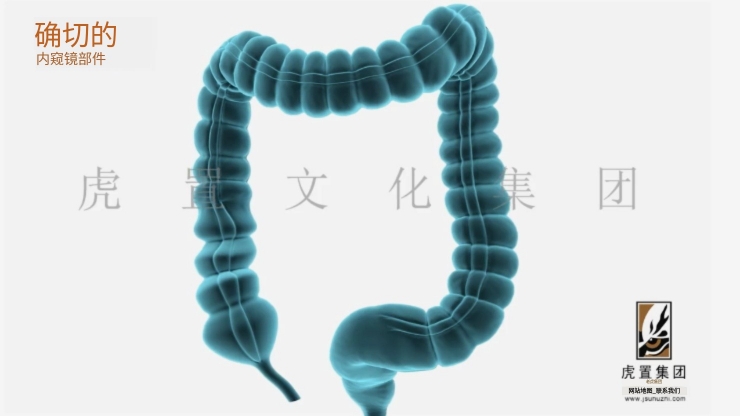

深耕于数字设计及展示领域的虎置文化集团成立20年,正努力成为全球知名的数字设计及展示服务商,为客户提供设计、展示及施工的一站式服务,为不同行业客户提供基于文化创意服务的整体解决方案。设计包括:建筑设计、景观设计、规划设计、展馆设计、室内设计、BIM设计;展示包括:三维动画、全息展示、影视广告、数字展馆、二维动漫、3D仿真效果图、VR&AR、企业宣传片等;施工包括:展馆展厅、室内装饰、幕墙工程、亮化工程。

公司依靠先进的三维动画制作技术,致力于三维动画的定制和制作,为数百家企业制作了各种类型的三维动画,有着丰富的实践经验和服务水平,制作的三维动画具有更灵活的表现形式、更强大的说服力和更生动的效果,成为众多企事业单位宣传产品、拓展市场、塑造品牌影响力的重要工具。服务政府、部队、世界五百强企业百余家;服务“一带一路”、“中国 制造2025”等重大国家战略项目;服务美国斯坦福、上海同济大学等国内外知名高校。